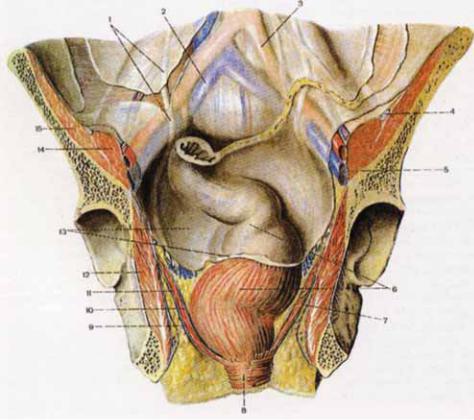

Анатомия малого таза: детальные схемы и изображения